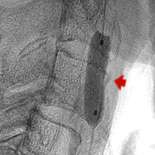

We do this with a small, soft balloon placed in the artery. With the balloon in place and inflated, we can then perform a neurological examination on the patient to make sure there is no problem. If the blood flow is insufficient, the patient will start to develop neurological impairment, such as weakness, loss of sensation, speech problems, etc.